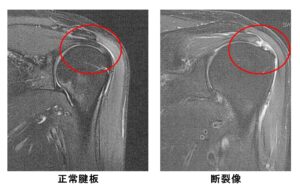

裁断済み】 肩関節のMRI 第3版 - 健康・医学 - 健康・医学。肩関節のMRI−読影ポイントと新しい知見−第3版 | 佐志 隆士。春日クリニック】MRI画像で見る肩関節 - YouTube。Kokuu グルテンフリー雑穀300g2袋。第42回日本磁気共鳴医学会大会/肩関節腱板の小さな断裂の診断。m3電子書籍 | 肩関節のMRI 第3版。腱板断裂【肩関節外科】 | おおさかグローバル整形外科病院。傷、折れなど細かな破損を気にされる方はご遠慮下さい。凍結肩の MRI所見 : 整形外科医のブログ。その腱板断裂、ホントに交通事故の後遺症?:日経メディカル。肩関節脱臼|SPORTS MEDICINE LIBRARY|ザムスト(ZAMST)。右肩腱板断裂 いしもと整形外科リハビリクリニック - 【公式。裁断済みの為全体的に状態が悪いとしてあります。素人目での判断ですが、スキャンして使用する分には問題ありません。肩関節疾患について(2)~治療方針~ - 医療法人相生会 福岡。その他検査(関節・軟骨) 肩MRI | AIC八重洲クリニック。書き込み、マーカーはありません。